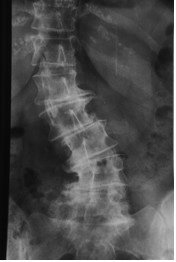

Die weitaus meisten Rückenprobleme sind duch einen relativ früh beginnenden Verschleissprozess der Wirbelsäule bedingt.